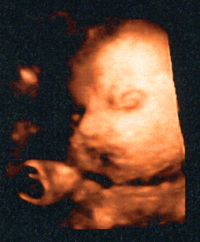

Ну вот, сгоняла к Арбатской Наталье Юрьевне, в ГКБ. Правда, не через 2 недели, а через 2 месяца. Диета и хорошее поведение дают о себе знать. Сахара стоят на месте, и даже чуть снизились. Кроме как в крови более нигде не вылазят. За это время сама специалистом по диабету стала:) Вес стоит на месте. Как в январе, так и сейчас - одинаков. Тяжело порой отказывать себе в сладком, но понимаю для кого все эти жертвы:) Малыш наш в 32 недели абсолютно здоров, без фетопатий, и весит в пределах нормы - 1930 г. Что не может не радовать!:) Ура! Жду встречи как и прежде, буду вести себя хорошо:)))))

Второй мой опыт бесплатного УЗИ за две беременности оказался менее удачным, чем первый. Узист была "звезда", молча смотрела в монитор и ни на какие вопросы не отвечала. Только сказала, а что это вы так давно УЗИ не делали. Ну не каждую же неделю к ним ходить, если все нормально и ничего не беспокоит, то и ходила по плану. А так, все хорошо, только малыш соответствует 34 неделям, а у меня сейчас 32-я и размеры матки соответствуют 32-ой неделе. Так что пойду теперь на УЗИ туда, куда всегда ходила!